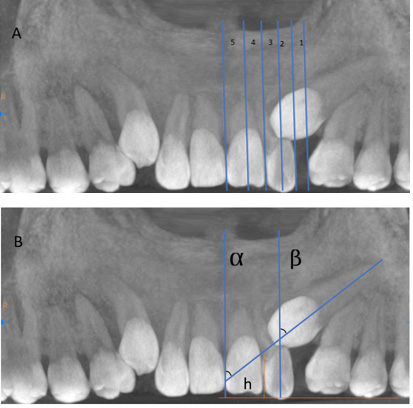

The position of the impacted maxillary canine (palatal, buccal or mid-alveolar), as well as the location of the impaction, whether unilateral or bilateral, were established. In addition, the sector of impaction was registered as follows according to the Erikson and Kurol classification:22 sector 1 – between the mesial side of the first premolar to the distal side of the lateral incisor; sector 2 – between the distal side of the lateral incisor and its median axis; sector 3 – between the median axis of the lateral incisor and the distal side of the central incisor; sector 4 – between the distal of the central incisor and its median axis; and sector 5 – between the median axis of the central incisor and the dental midline (Figure 1A).22, 23, 24, 25

The height of impaction in millimeters in relation to the occlusal plane, as well as the angulation of the impacted maxillary canine in relation to the mid-sagittal plane (the alpha angle) and to the medium axis of the lateral incisor (the beta angle), were also measured (Figure 1B).22